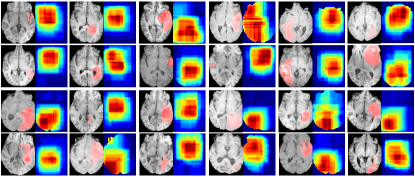

Refer to caption

Figure 8: The heatmap (the probability of brain regions which can achieve the lowest MAE) of each brain shows the brain age evidence extracted from local patches. The chronological age is highlighted in red color and the MAE range (minimum-maximum predicted errors) is shown in white color.

In this section, we propose two types of interpretation: subject-level interpretation which highlights the most discriminative patches on each subject and group-level interpretation which shows the most salient brain regions over a group of subjects within a certain age range. For subject-level interpretation, the 5 patches with the lowest MAEs of each patch size are collected and a heat map is built for visualizing the most informative regions. For group-level interpretation, we only select the 5 patches on each subject with the lowest MAEs of patch sizes 32 and 40, and then all selected patches from subjects within the age range are averaged to obtain a fine-grained heatmap. The heatmap shows the probability that the lowest MAE (the best prediction) can be obtained on the brain image.

Fig. 8 shows the most informative brain regions on each subject computed by averaging the patches with the lowest MAEs with various patch sizes. For each brain MRI, the most patches with the lowest MAEs covers the same region, indicating that the salient region (shown in Fig. 8) contains the most brain age information than other brain regions. In addition, the salient brain age regions are slightly different among subjects with different ages. To compute the general trends of the salient brain age regions, we average the salient regions on subjects within a certain age range and the results are show in Fig. 9. There is a trend of the changes of the salient brain regions over time. In the children (0-5 years old), the most salient brain age region is on the frontal lobe. It shifts to the deep gray nuclei region with age range of 5-20 years. Starting at 20 years, the salient region is gradually shifts to the parietal lobe at 30-35 years old and then shifted back at 35-40 years until 65-70 years. After 75 years, there are two salient regions which contain the most age information.

Figure 9: The average heatmaps of subjects on different age ranges. The heatmap shows the probability (red means high probability and blue means low probability, as shown in the color bar on the right) of brain regions which can achieve the lowest MAE on each age group. The MAE range (minimum-maximum predicted errors) is shown in white color.